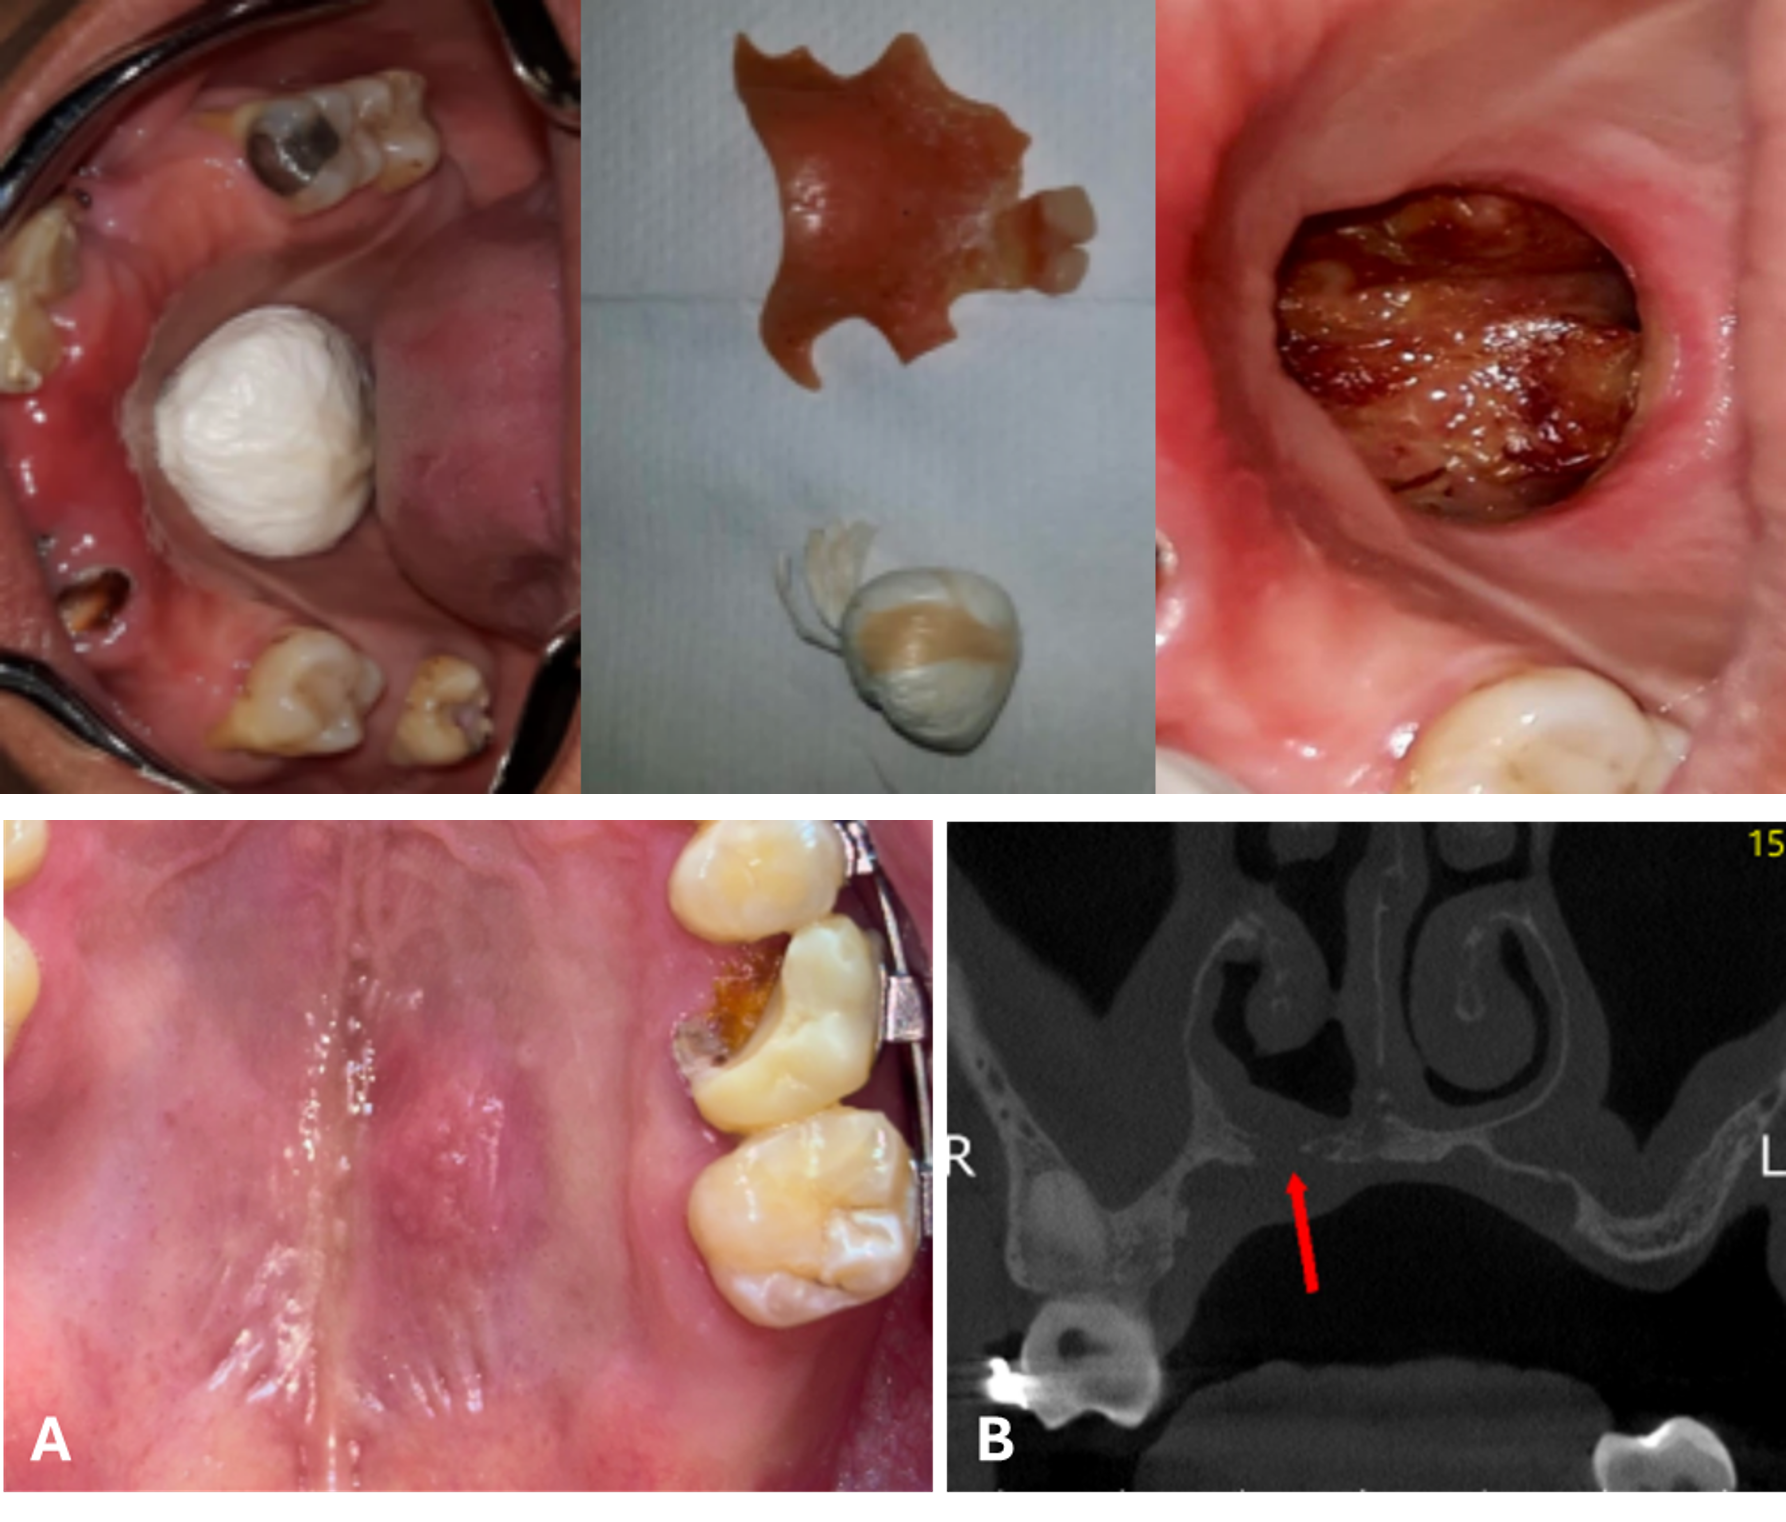

Hospital Dentistry Approach to a Patient with Mucormycosis treated with Amphotericin B: Case Report

George Matos Ferreira Gomes Júnior, Ivyna Maria Cardins Falcão, Carla Welch da Silva, Isaac Müller de Sousa Maia, Camila de Oliveira Lobo, Luanda Ashley Menezes Estácio, Jonas Nogueira Ferreira Maciel Gusmão, Daniel Facó da Silveira Santos, Eliardo Silveira Santos